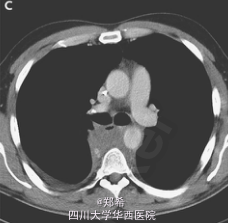

遂活检,显示为精原细胞癌。患者接受了3周期博来霉素、斯托泊苷、顺铂化疗后,肿块缩小明显。

患者随访10年,无任何症状且每4个月随访一次。精原细胞癌转移至纵隔较为少见,且本例患者化疗效果较为理想,值得参考学习。N Engl J Med August 21, 2014。DOI: 10.1056/NEJMicm1314944